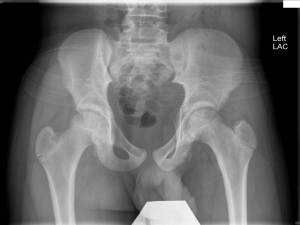

And so, today I wanted to share with you a ‘Practical Management’ research article that was just published via PAP: “Surgical Management of Traumatic Avulsion of the Ischial Tuberosity in Young Athletes,‘ by Roland M. Biedert, MD.

I was particularly interested in this article, as I see many adolescent athletes and pelvic apophyseal injuries arrive at our clinic in droves. It is rather uncommon to see an acute, purely tendionous injury in my clinic population: last week when I saw an acute rupture of the proximal long head of the biceps tendon, in a 17-year-old pole vaulter, I was intrigued indeed! The acute achilles tendon rupture in my clinic makes me wonder whether a fluoroquinolone has been used recently; seeing a patient in my own age group, I’d more likely say, c’est la vie…..

The more common story in my day-to-day clinical world is for a chronic or acute injury to the apophyseal cartilage, to which a muscle-tendon unit attaches. The tendon holds, I tell a patient; it is its attachment to the growth cartilage that gives way.